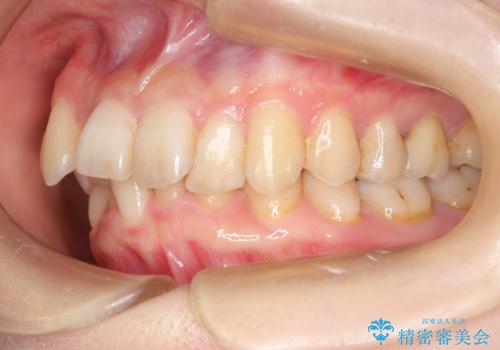

- 前歯の見た目の改善を希望され来院された患者様です。

初診時の歯並びの状態としては、上下ともに前歯部の中等度のがたつきがあり、下の前歯は本来生えるはずの歯が2本生まれつき欠損している状態でした。

抜歯ありワイヤー矯正にて治療を行い、抜歯する歯に関しては虫歯で抜歯が必要な部分を有効活用することで、健康な歯を保存するように努めました。

噛み合わせが深い過蓋咬合という状態でもあったため、下の歯の装置をつけたり、嚙み合わせを上げる(下の歯が見える状態にする)ことにたいへんに苦労した症例でした。

見た目、嚙み合わせ及び、治療期間や施術内容に大変ご満足いただきました。